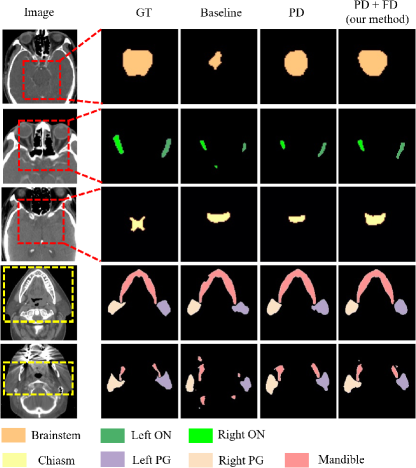

The difference learning introduced in the first stage can enhance the model’s ability to segment the current organ, improve the distinctiveness of different student models, and enhance the quality of the generated pseudo labels. To evaluate its effectiveness, we conducted extensive ablation studies and analyzed the following aspects:

Metric. Table V compares mean DSC across models. After introducing the label-level difference mutual learning loss (PD), the DSC for all body parts were improved, especially with the DSC of chest increasing to 90.05 (an increase of 1.06). The addition of feature-level difference loss (FD) further improved the average DSC to 78.62 (head and neck), 90.07 (chest), 90.43 (abdomen), and 89.37 (pelvis), demonstrating that incorporating information from other datasets can enhance the segmentation performance of the current model.

Pseudo-Label Analysis. To verify that the introduction of Prediction-level Difference (PD) and Feature-level Difference (FD) can produce higher-quality pseudo labels, we took the head and neck PDDCA and StructSeg datasets as examples. The models trained on these datasets are referred to as and (partial-organ segmentation model), respectively. generated pseudo labels for the brainstem and left and right optic nerves on the StructSeg dataset, while generated pseudo labels for the chiasm, left and right parotid glands, and the mandible on the PDDCA dataset, and then compared these with the true labels of the two datasets. The DSC between the pseudo labels and the true labels showed that, without the introduction of difference learning, the average DSC for the seven organs was 56.67 (53.95 for PDDCA, 58.70 for StructSeg). Introducing PD loss increased the average DSC to 57.64, with a particularly significant improvement in the PDDCA dataset, rising to 57.17 (an increase of 3.22). Further introducing feature difference loss (PD + FD) improved the average DSC to 58.44, with PDDCA rising to 57.87 and StructSeg to 58.88. Fig. 8 also shows that the pseudo labels generated with label and feature difference losses more closely resemble the true labels, especially for organs such as the brainstem and mandible, indicating that the introduced difference learning enable the model to perceive the presence of other organs, thereby generating higher quality pseudo labels on other datasets.

Feature Visualization. To verify that the difference learning can make the features of different organs extracted by different models more distinguishable, we used t-SNE to visualize the high-dimensional features extracted by different models on the same dataset. As shown in Fig. 9, without difference learning (Fig. 9 (a)), the features of different organs significantly overlap, which reduces the segmentation performance of the model and the quality of the pseudo labels. Introducing PD loss (Fig. 9 (b)) provides some distinguishability among the features of different organs, but overlap still persists. After adding FD loss (Fig. 9 (c)), the features of different organs are clearly separated, leading to higher precision in segmenting different organs by different models, and also improving the quality of pseudo labels generated on other datasets, significantly reducing the occurrence of overlap with labels from other organs.

IV-D2 Effectiveness of Similarity Mutual Learning

In the second stage, we conducted an ablation study to verify the effectiveness of the proposed similarity learning, as shown in Table VI. The baseline model was trained under the supervision of combined labels, achieving an average DSC of 77.34 (head and neck), 88.72 (chest), 88.63 (abdomen), and 90.30 (pelvis). The introduction of LS improved the average DSC, especially for the abdomen, increasing by 1.37. Further addition of the FS (especially DFS) brought the average DSC to 79.29 (head and neck), 90.94 (chest), 90.74 (abdomen), and 90.99 (pelvis). These results confirm that similarity learning can fully utilize the true labels of other datasets, increase supervisory information, and enhance the performance of multi-organ segmentation.

IV-D3 Effectiveness of DFS

We also evaluated dynamic feature similarity mutual learning in the second stage (Table VI). Comparing with static feature similarity mutual learning, our proposed DFS outperformed it across all regions: it improved mean DSC by 1.37 (head and neck), 1.1 (chest), 0.53 (abdomen), and 0.29 (pelvis). This demonstrates that DFS effectively transfers correct knowledge, enhancing model supervision and performance.